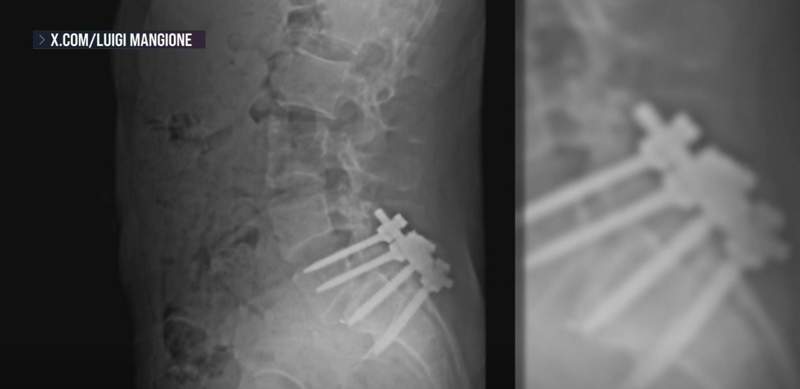

Посты на «Reddit» также свидетельствуют о том, что владелец аккаунта перенес операцию по сращению позвоночника в 2023 году.

Операция по сращению позвонков заключается в установке кости или материала, похожего на кость, в пространство между двумя позвонками, а затем соединении трансплантатов и костей металлическими пластинами, винтами или стержнями. Цель состоит в том, чтобы срастить кости для того, чтобы уменьшить давление на позвонки и укрепить форму и устойчивость позвоночника. Этот тип операции на спине может значительно уменьшить боль, хотя восстановление может занять до года, поскольку костные трансплантаты срастаются с позвонками. Исследование 2022 года показало, что из примерно 100 пациентов, перенесших операцию, около 85-90% сообщили об удовлетворенности.